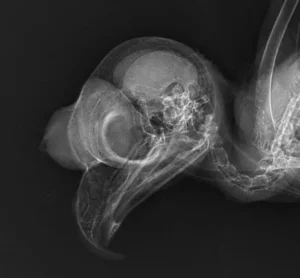

An owl’s skull is easily identified by its sizeable eye sockets that accommodate its large eyes. This allows the raptors to see well in dimly lit conditions. Owls can rotate their heads up to 270 degrees in either direction, granting them a wide range of vision without having to move their bodies.